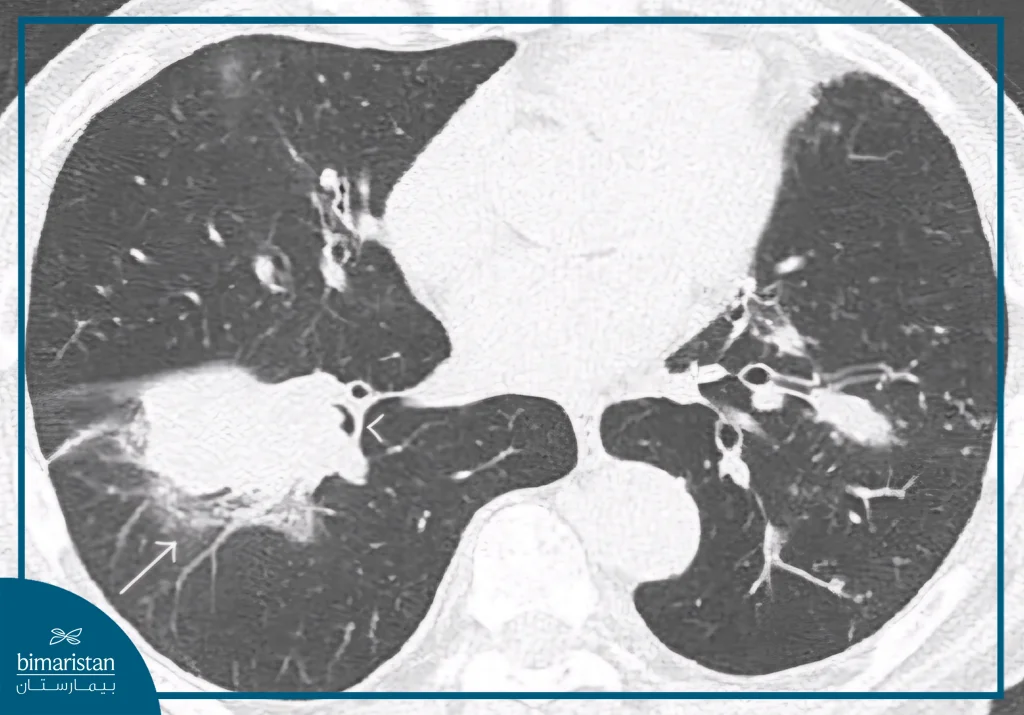

Squamous cell lung cancer is usually diagnosed after a lung mass is suspected as a result of persistent respiratory symptoms or during an imaging test conducted for another reason. In some cases, the tumor is discovered accidentally during a CT scan or a routine chest X-ray. Medical authorities also recommend early detection with low-dose CT scans for people between the ages of 50 and 80 with a long history of smoking, as this helps detect the disease in its early stages and improves the chances of treatment.

- Computerized tomography (CT) scan: To accurately assess the size and extent of the tumor.